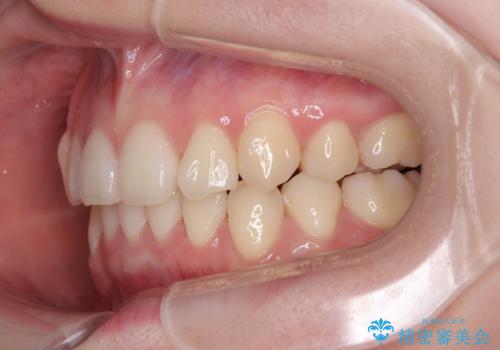

上下の八重歯とクロスバイト ワイヤー装置での抜歯矯正

20歳ということもあり、歯の移動速度が非常に速く、1年強という短期間であっという間に治療を終えることができました。